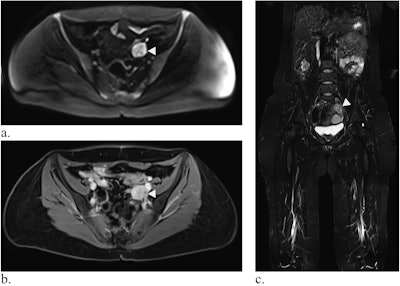

Whole-body MRI of a 39-year-old woman with LFS showing a mass in the small pelvis (white arrow) in diffusion-weighted imaging (a) and contrast-enhanced T1-weighted Dixon images (b, here: water-only image). In the coronal TIRM-sequence (c), the mass is visible, but difficult to differentiate from the intestine, emphasizing the value of diffusion-weighted imaging. Histology revealed a leiomyosarcoma.

Whole-body MRI of a 39-year-old woman with LFS showing a mass in the small pelvis (white arrow) in diffusion-weighted imaging (a) and contrast-enhanced T1-weighted Dixon images (b, here: water-only image). In the coronal TIRM-sequence (c), the mass is visible, but difficult to differentiate from the intestine, emphasizing the value of diffusion-weighted imaging. Histology revealed a leiomyosarcoma.